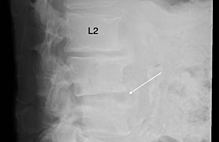

Superficial incisions were made to dissect the skin and deep fascia off completely. The superior and inferior extensor retinacula were cut to expose the tendons. The tendons of the extensor digitorum longus, tibialis anterior, extensor hallucis longus, fibularis longus, and fibularis brevis were cut at their insertions. The muscle belly of the extensor digitorum brevis and its tendons were cut to expose the underlying bones and ligaments. The length of the foot was measured using a ruler from the most posterior end of the calcaneus to the most anterior end of the second distal phalanx. Its width was measured with a ruler at the level of the metatarsal heads. The subtalar joint was cleaned with a probe to expose the CL clearly. The width and height of the cervical ligament (Figure 1-2) were measured. Its thickness was measured at the superior anterior, superior posterior, inferior anterior, inferior posterior and center points with a digital caliper (Hawk Inc., Cleveland, Ohio). The width and height of the talar neck were measured using a digital caliper (Hawk Inc., Cleveland, Ohio). The body of the talus was cut in the frontal plane and its proximal portion was removed to expose the ITCL (Figure 3). Descriptions of the ITCL were recorded for each cadaver.